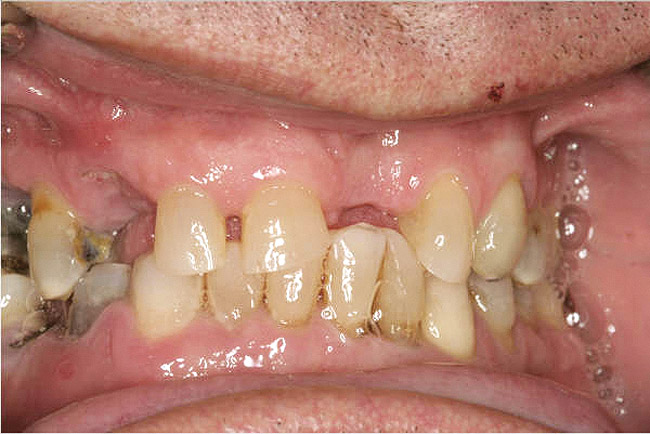

It is also important to explain to patients that the health of their gums is assessed every time they come in; but at this point in time, there are some areas of bleeding on probing, with pockets of disease around their teeth greater than 3 mm deep. It must also be communicated that this is a sign of infection in their gums and that it should be treated immediately (Figure 1).